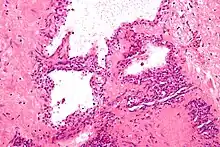

| Micrograph showing a pancreatic serous cystadenoma. H&E stain. | |